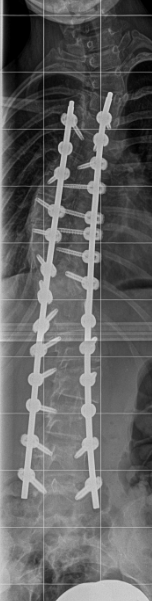

Im Juni 2021 fand dann die OP statt, bei der fast meine gesamte Wirbelsäule versteift wurde.

Komplikationen hatte ich auch sonst keine. Trotz der schwierigen Phase nach der Operation ist diese Zeit nicht vergleichbar mit den Jahren davor. Ich bin Dr. Desai sehr dankbar und würde mich jederzeit wieder für diesen Eingriff im Sana-Krankenhaus in Köln entscheiden. Besonders beeindruckt bin ich noch heute davon, wie stark Dr. Desai meine ausgeprägte Skoliose korrigieren konnte.